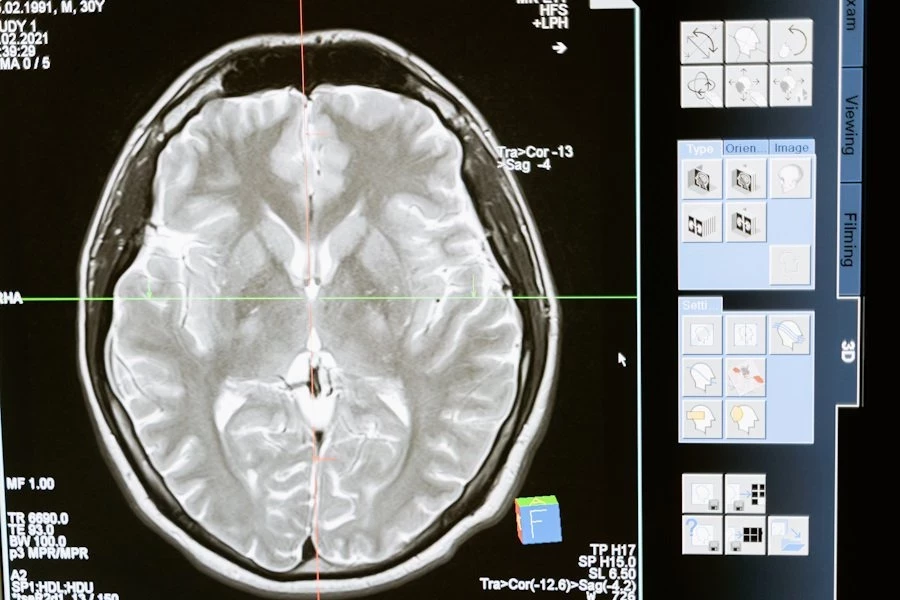

Для анализа использовались данные визуализации мозга 10 949 человек в возрасте от 45 до 82 лет и образцы крови почти 5 000 участников. Учёные также подтвердили причинно-следственную связь между уровнем BCAN и ускоренным старением мозга с помощью генетического метода Менделевской рандомизации.

Полученные данные открывают новые горизонты в борьбе с возрастными заболеваниями мозга, такими как деменция. Разработка методов ранней диагностики на основе анализа крови может заменить более сложные процедуры визуализации, сделав скрининг доступным и неинвазивным. Авторы исследования подчёркивают важность дальнейшего изучения поведения этих белков в различных возрастных и этнических группах, чтобы сделать выводы универсальными.